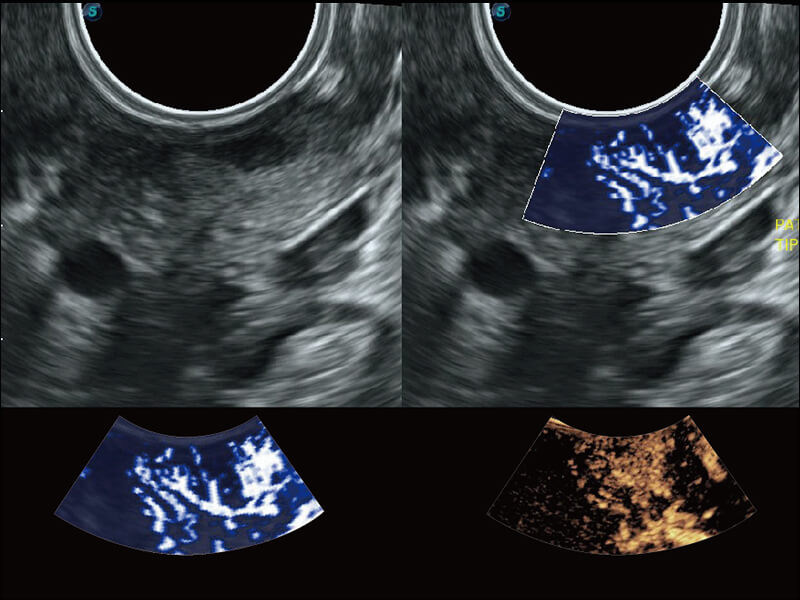

S60探头工艺,从前端信号处理每一个环节采集无损声学数据,真实还原组织原貌,再现解剖细节。

超宽频带技术,为容积成像带来优质的二维图像基础,为您呈现丰富的结构细节,栩栩如生地展示宝宝的宫内形态以及各种组织的立体结构。